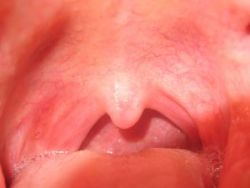

Mandulagyulladás kisgyerekeknél

Mandulagyulladásra

"Rendszeresen gond van a mandulámmal, és minden évben ki akarják venni. Nem szeretnék több gyógyszert szedni, de a műtéttől tartok." Amikor úgy érzi…

A mandulagyulladást teafával kezelheti, 1 cseppet hígítva kenve külsőleg a mandula, torok területre. Érdemes kiegészíteni homeopátiával (én a Bellad…